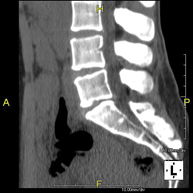

- Thoracic spine CT

Radiological test that involves capturing high-definition anatomical images of the thoracic vertebrae using a CT (computed tomography) scanner. Indicated for: acute/chronic back pain, trauma, spinal misalignment.